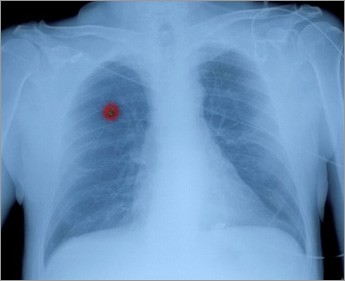

Συχνές ερωτήσεις και απαντήσεις για τον καρκίνο του πνεύμονα

Ορισμένες φορές η ανακάλυψη του όγκου είναι τυχαία, οπότε ο ασθενής είναι ασυμπτωματικός.